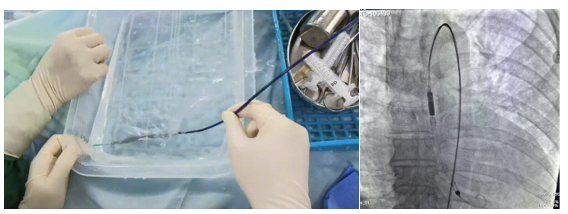

其自主研发的D-OmniHeart已于2022年8月完成全国首例植入,成功救治一名危重终末期心衰患者。

图 D-Omniheart试运行及植入影像